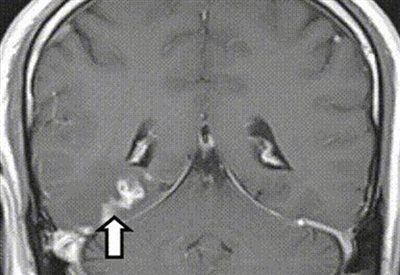

Οι μαγνητικές τομογραφίες αποκάλυψαν μια ανωμαλία στο δεξί εγκεφαλικό ημισφαίριο, ωστόσο η βιοψία που ακολούθησε δεν έδειξε όγκο. Όμως οι μαγνητικές τομογραφίες που ακολούθησαν τα επόμενα τέσσερα χρόνια έδειξαν την ανωμαλία να κινείται σε απόσταση πέντε εκατοστών και να περνά στην αριστερή πλευρά του εγκεφάλου.